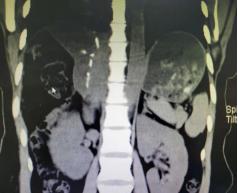

(术前VS术后的影像图)

术中见肝血管瘤巨大,位于右肝6、7、8段,左肝2、3段,且右肝的肿块压迫肝中静脉。